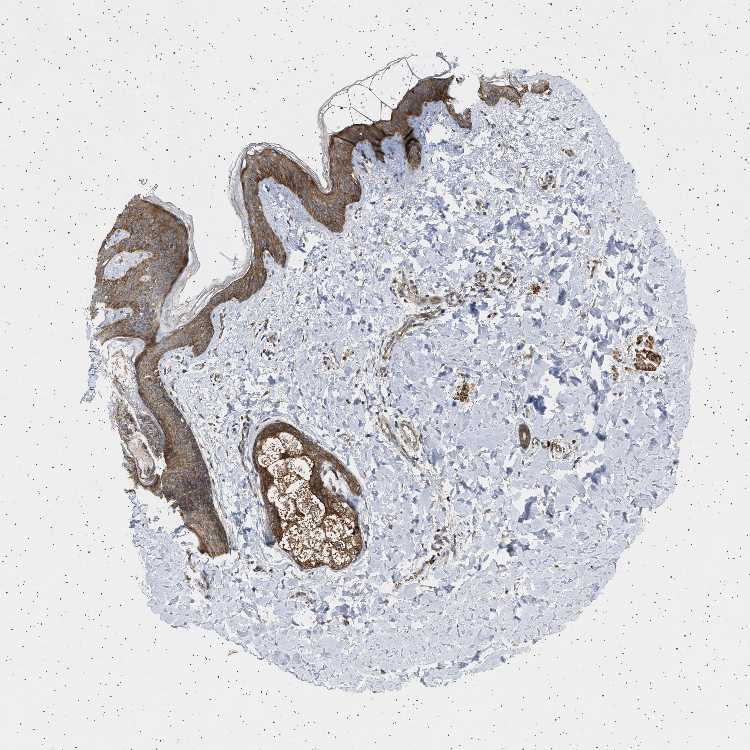

SKIN 1 - Antibody stainingi

Antibody staining in the annotated cell types in the current human tissue is reported as not detected, low, medium, or high, based on conventional immunohistochemistry profiling in selected tissues. This score is based on the combination of the staining intensity and fraction of stained cells.

Each image is clickable and will lead to virtual microscopy that enables deeper exploration of all samples and also displays staining intensity scores, fraction scores and subcellular localization as well as patient and tissue information for each sample.

Antibody HPA014569Antibody HPA018019

Langerhans MediumHigh

Fibroblasts -Medium

Keratinocytes MediumHigh

Melanocytes MediumHigh

SKIN 2 - Antibody stainingi

Epidermal cells MediumHigh